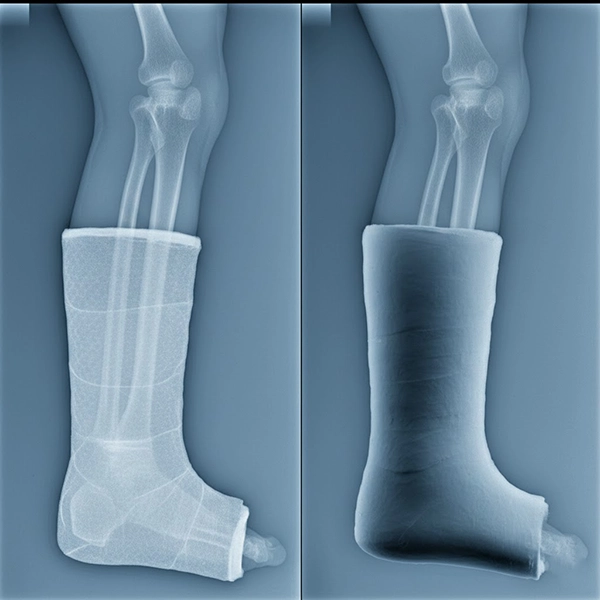

نمای رادیولوژی از اندام گچ‌گیری‌شده با باند فایبرگلاس که جزئیات استخوان را با شفافیت بالا نشان می‌دهد

مقایسه نمای رادیولوژی: رادیولوسنسی بالای فایبرگلاس در برابر سایه‌دهی بیشتر گچ POP